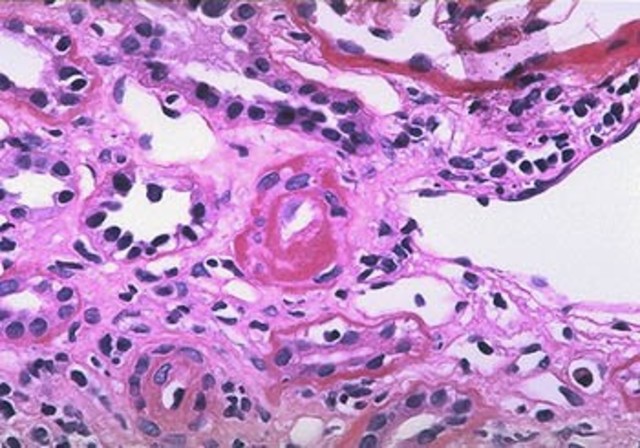

Autopsia es realizada en la tarde del 21 de abril. Se encuentran hallazgos macroscópicos importantes en riñones, corazón, colon y paratiroides

Llegan los resultados microscópicos de patología.